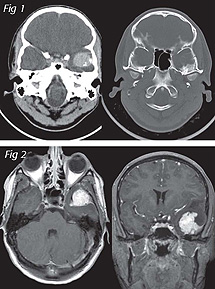

21y.o. female presented with progressing stabbing headaches of three weeks, nausea, and vomiting. Her medical history and physical and neurological exams were unremarkable. Infused CT revealed a homogeneous enhancing lesion in the left middle cranial fossa. The greater sphenoid wing looked remodeled (Fig 1).

An enhanced MRI showed well-demarcated margins of the lesion and dural tail sign (Fig 2). Angiography revealed hypervascular lobulated tumoural blush, and persistent staining. The main arterial supply was arising from enlarged middle meningeal and accessory meningeal branches (Fig 3).

Capillary hemangiomas (CH) are frequent tumours in children and in 50% of the cases affect the head and neck. The CNS is a rare location for these tumours, and most cases reported involve the spinal cord of adults.2 The descriptions of isolated intracranial CH are scarce. They may involve the brain parenchyma or the dura. Our case adds to the short list of intracranial dural CH. The CT and MRI features in dural CH are similar to those of meningioma, and the literature does not seem to identify characteristics that would allow imaging differentiation between these lesions. In our patient the presence of a dural tail favored meningioma, however, the bone remodeling and the angiographic appearance (Figs. 1,3) lead us to consider hemangiopericytomas, hemangiomas, and angiosarcomas in the differential diagnosis. Histopathology confirmed the diagnosis of CH.1,2,3 (Photomicrograph Fig 4)